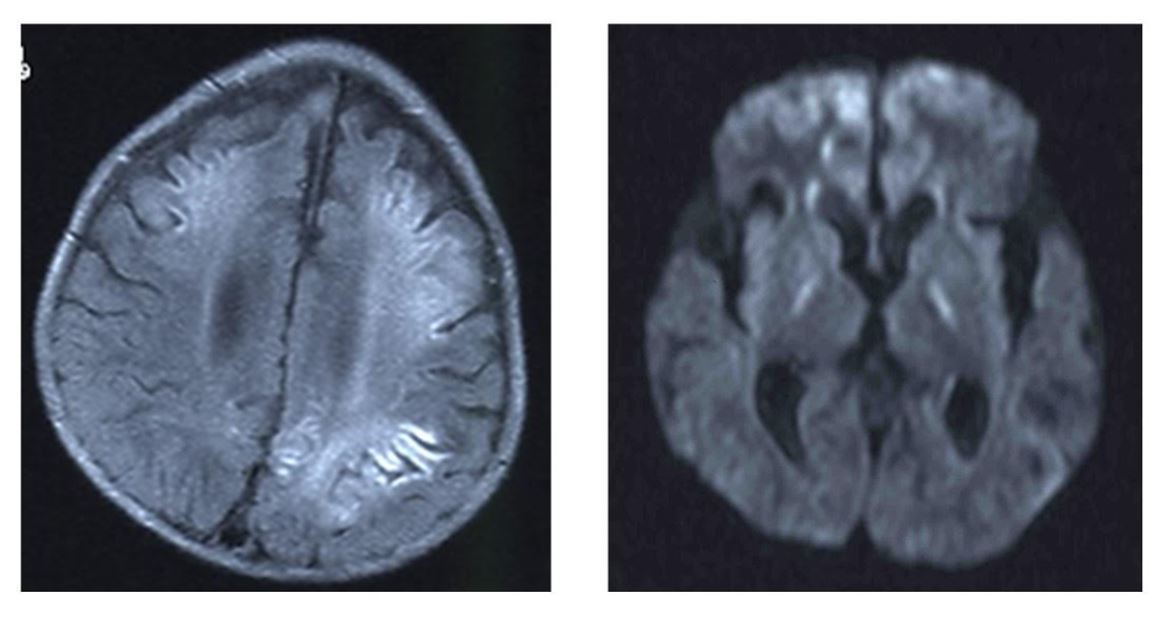

Liver analysis was performed 8 days after admission. Liver pathology revealed mild infiltration of inflammatory cells. There was neither fibrosis nor cholestasis. Prominent accumulation of lipid droplets of various sizes was observed (Figure 2).

Prominent accumulation of lipid droplets of varying sizes were observed. In the 2,500 X electron microscopy images of the liver, lipid droplets of various sizes were distributed almost uniformly within the cytoplasm of liver cells, together with the almost complete disappearance of intracellular structures (Figure 3).

Figure 2: Hematoxylin-eosin (HE) staining of liver tissue

Prominent accumulation of lipid droplets of varying sizes were observed.